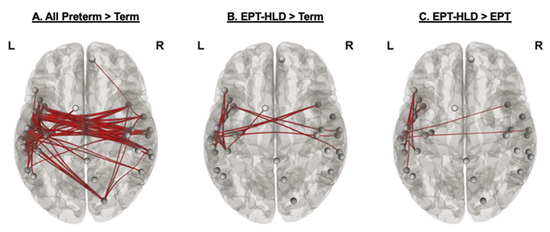

3.4. Network Strength and Relation to Performance

3.4.1. All Extremely Preterm Children versus Term Children

3.4.2. Extremely Preterm Children without History of Language Delay or Deficit (EPT)

3.4.3. Extremely Preterm Children with History of Language Delay or Deficit (EPT-HLD)